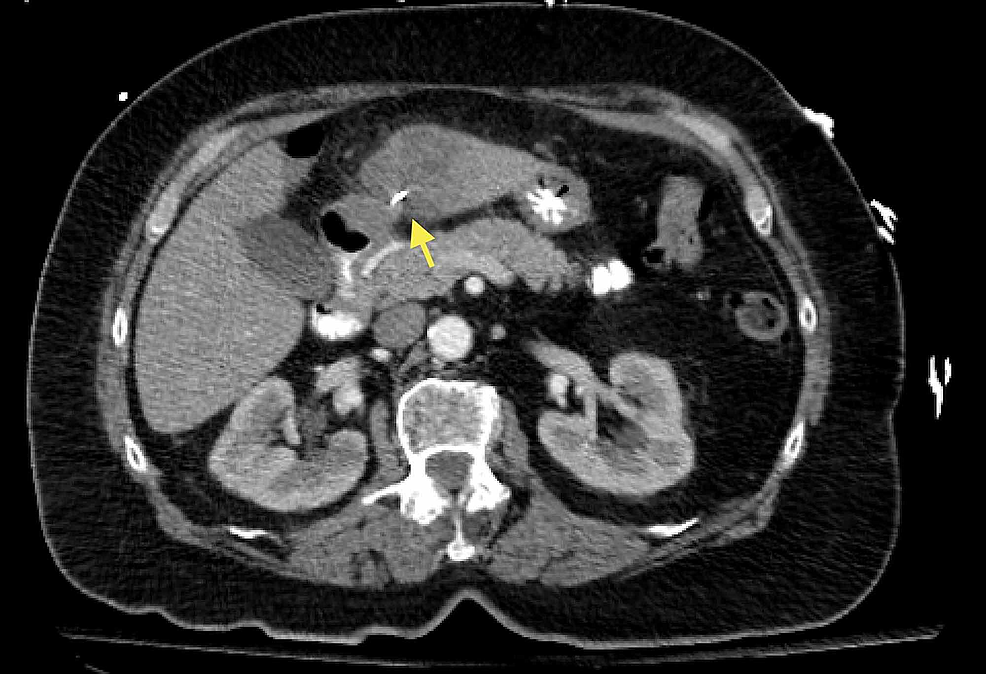

Cureus | Liver Abscess Caused by Ingestion of a Sewing Needle

Liver abscess is a common medical emergency prompt empirical antimicrobial with or without percutaneous aspiration or drainage of the abscess is therapeutic an empiric antimicrobial regimen for liver abscess should cover enteric gram-negative bacilli, streptococci, anaerobes and antamoebahistolytica. One reason for this problem is that it is common that pus from a liver abscess is collected after administration of antibiotics. 1 this may lead to an under-estimation of bacteria causing liver abscess and may also contribute to a gap in physician knowledge to determine which antibiotic is most appropriate for treatment. this raises another issue of selection bias, where the positive culture results may have a more resistant profile if patients had received antimicrobial therapy prior to. The management of pyogenic liver abscesses usually requires 4 weeks of antibiotic therapy. it is unknown if oral (po) antibiotics are as effective as intravenous (iv) antibiotics for this indication. objectives.